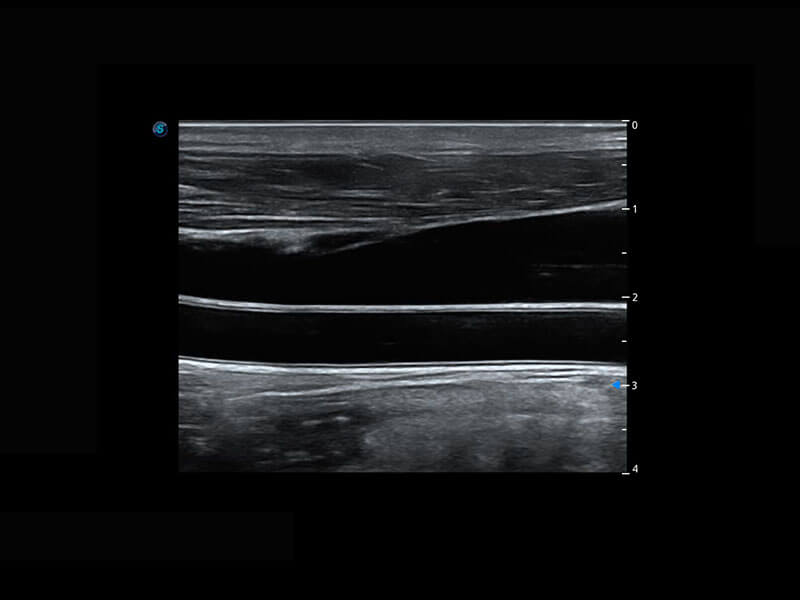

P60优异的图像质量搭载专科探头,在妇科基础疾病的诊断、卵泡生长的监测、输卵管通畅情况的判别等方面为您提供生殖应用方案。

腔内妇科-宫腔分离

腔内妇科-卵巢

腔内三维-宫内节育器

腔内三维-光影成像